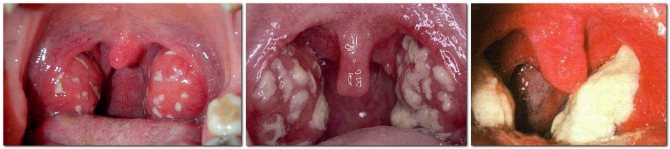

На фото фолликулярная, лакунарная, фибринозная ангина

Налет на миндалинах – один из основных симптомов их воспаления. Он может иметь разный цвет, зависимо от стадии и специфики заболевания, которое прогрессирует: белый, серый, желтый, могут появляться гнойники и все это сопровождается острой болью в горле. Если не обращать внимания на пленку на гландах, то в скором времени болезнь распространится, и вы заработаете ангину, или дифтерию, воспаление носоглотки и даже болезни сердца, долго лечащиеся и имеющие много негативных последствий. Поэтому, когда появляются первые симптомы налета на миндалинах, ухудшается самочувствие, поднимается температура и горло начинает болеть – немедленно отправляйтесь к врачу! Никогда не занимайтесь самолечением. В домашних условиях вы можете только облегчить свои страдания, прополоскав горло солевым или спиртовым раствором, Фурацилином.

Как уже было сказано, налет на миндалинах, может иметь различный оттенок, начиная от белого, заканчивая грязно-серым, поэтому в случае его появления лучше не пытаться самостоятельно установить цвет, а обратиться к отоларингологу, который, опираясь на знания и врачебную практику, сможет достоверно определить оттенок пленки. Это очень важно для точной диагностики заболевания, так как, например, белый налет на миндалинах может быть признаком таких заболеваний, как ангина, скарлатина, стоматит, дифтерия, кандидоз и другие. Для более четкой диагностики врачи берут мазок, чтобы определить природу микробов и назначить подходящее лечение.

Гнойный налет на миндалинах

Эго в народе называют «гнойной ангиной». Это зачастую острый тонзиллит, запущенный на ранней стадии, когда уже из простой пленки образовался гной. Сопровождается высокой температурой, очень плохим самочувствием человека, общей слабостью, головной болью, отсутствием аппетита.

Существует несколько форм дифтерии зева и, соответственно, несколько разных видов пленок. При локализованной форме дифтерии налет на миндалинах практически не виден, скорее он похож на пленку с перламутровым сероватым блеском. Когда человек болен токсической дифтерией, пленка представлена грязно-серыми корками на гландах и очень болезненна. При распространенной форме дифтерии она может иметь цвет, начиная светло-серым, заканчивая темным оттенком, и локализируется не только на гландах, а и выходит за их пределы.